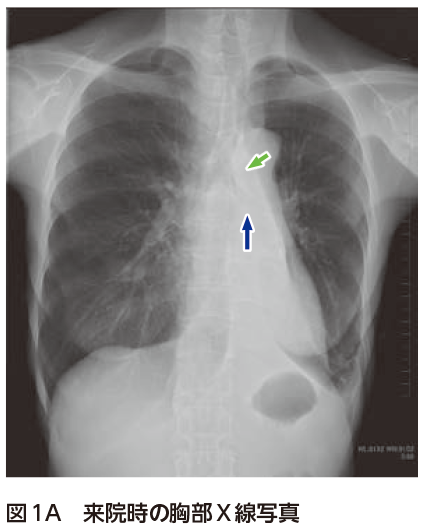

・背側肺の無気肺が改善 換気が均⼀化され肺傷害を回避 その結果として酸素も改善 腹臥位療法(PROSEVA study) p過去の研究では有意差なし pプロトコルを⼯夫 nP/F肺癌+下葉の限局性無気肺 下行大動脈のラインが見えない 過去画像があれば比較 1年前 肺癌 人工物に惑わされない! 肺癌 おまけ 人工物のx線像 (異物の誤飲、誤嚥) ボタン電池 チョーク 油性マジック のキャップ 積み木 あめ玉 乾電池 ガラス瓶 虫眼鏡 (プラスチックレンズ) ptpシート入院後経過:画像と気管支鏡所見より左上葉支完全閉 鎖による左上葉無気肺と診断した.1993年の検診時の 胸部x線を取り寄せて検討したところ,今回の腫瘤影 は認めないものの,左肺の肺紋理の減少と透過性亢進の 所見があり,この無気肺は以前より存在したものと考え られた.また,1996年